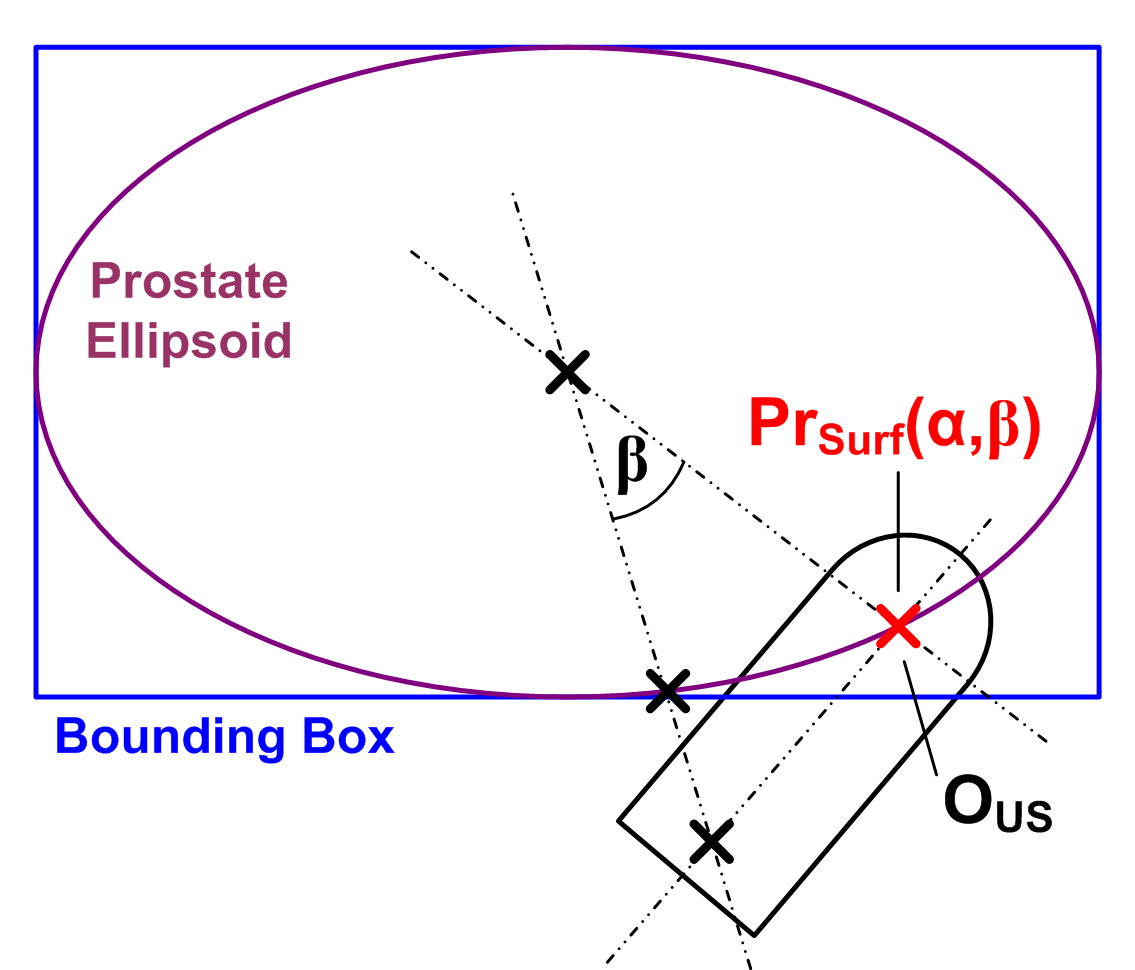

With these assumptions it is possible to define a probe movement model based on a prostate surface approximation, the probe position in the US image (which is known) and a rotational fixed point in the rectum. As shown in Fig. 1, the prostate surface is approximated by a bounding-box aligned ellipsoid. The ellipsoid is modeled using a 2D polar parameterization . The origin of the parameterization corresponds to the intersection of the line from the prostate center to . As illustrated in Fig. 1, implements assumption 1) by determining plausible US transducer positions on the prostate surface. Assumption 3) is satisfied by requiring that the principal probe axis must always pass through . Finally, a rotation about the principal probe axis implements assumption 2) and thus adds a third DOF (See Fig. 1).